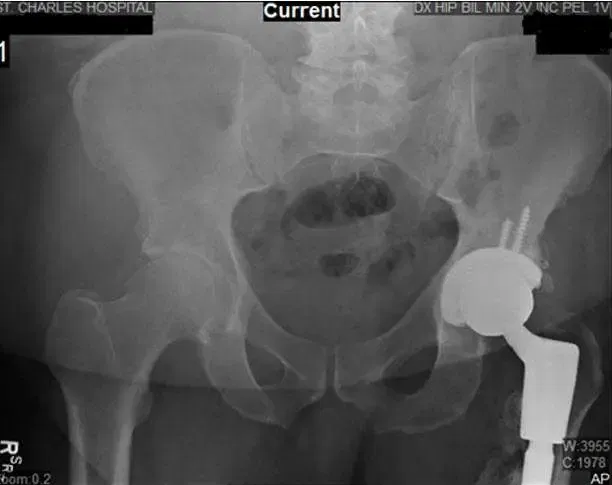

X-Ray of Bilateral Hip. X-ray shows Left THA along with new bone formation along the lateral and proximal shaft of the femur.

The patient had stated that he was feeling good relief from the pain medication. Upon examination, he was experiencing tenderness over the greater trochanter of both the lower left and lower right extremities. At subsequent follow-ups the X-rays reviewed were normal and showed that there was no acute displaced fracture and possible focal osteopenia of the loosening. The patient was advised to begin weight bearing as tolerated and continue Vitamin D3 5,000 IU daily.